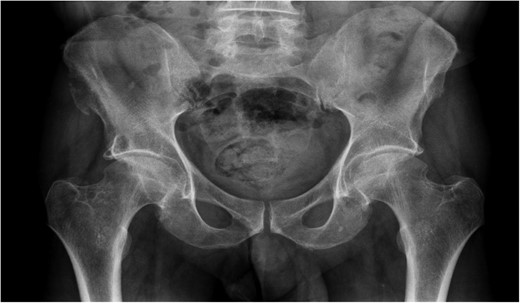

A previously fit and well 68-year-old male presented with a 6-month history of pain in the right hip. On examination this was localised to the superior area of the hip joint where a bony mass could be palpated. A pelvic radiograph was performed (Fig. 1) showing a bony exostosis on the right iliac wing. To characterise the lesion further, a pelvic Magnetic resonance imaging (MRI) scan was performed (Fig. 2). Appearances were consistent with an osteosarcoma and referral to the local sarcoma centre for histological investigation was made. Surprisingly, sampling from biopsy showed invasive well-differentiated adenocarcinoma. Staging computed tomography (CT) scanning did not reveal a primary source for the tumour but did identify thickening of the descending colon (Fig. 3) and lymphadenopathy involving the left supraclavicular, thoracic, paravertebral, retro-crurual and right inguinal regions. There was no evidence of tumour in the liver, lung or other parts of the skeleton. Subsequently, colonoscopy identified the thickened lesion as a hepatic flexure adenocarcinoma (Fig. 4). Biopsy at the time of endoscopy revealed the lesion at the hip to be a metastasis.

CT abdomen demonstrating thickened segment of ascending colon.